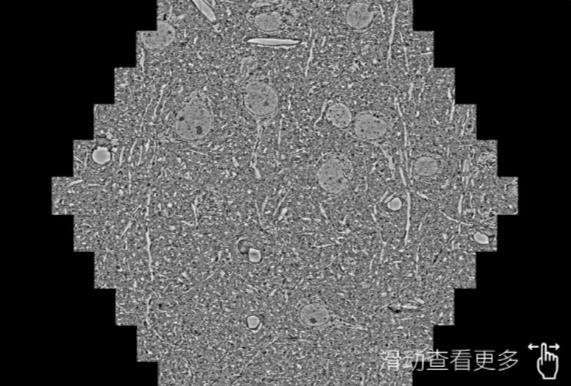

鼠脑切片。左图使用门头沟蔡司门头沟扫描电镜MultiSEM706对165μmx143pm面积区域成像,耗时仅需1.5秒。右图为鼠脑切片中30μm区域放大效果。样品由芝加哥大学B.Kasthuri提供。

使用蔡司高速门头沟扫描电镜MultiSEM对1mm²人脑皮层组织进行高分辨成像,并对其中的各种细胞结构进行三维重构分析。左图展示了2x3mm²组织平面中锥体神经元的三维重构效果。右图显示了局部体积神经元三维重构。图像由哈佛大学chtman实验室提供,渲染图由D. Berger 制作。